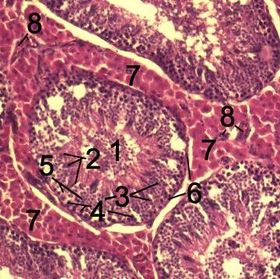

Histological section through testicular parenchyma of a boar. 1 Lumen of Tubulus seminiferus contortus 2 spermatids 3 spermatocytes 4 spermatogonia 5 Sertoli cell 6 Myofibroblasts 7 Leydig cells 8 capillaries | |